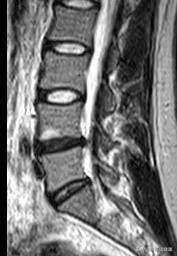

La hernie discale lombaire présente un symptôme appelé claudication intermittente. Bien que cette manifestation de sténose rachidienne lombaire puisse être trouvée lors d'une IRM, vous ne pouvez pas la diagnostiquer aveuglément comme une sténose rachidienne lombaire car la plupart des claudications intermittentes causées par une sténose rachidienne lombaire sont bilatérales et symétriques, et non une douleur unilatérale !

Lorsque ce problème survient, il ne faut pas se précipiter sur les résultats du scanner ou de l'IRM, la hernie peut présenter une sténose rachidienne lombaire dans le grand rapport, mais cela ne signifie pas que la sténose rachidienne provoquera des symptômes, le nucleus pulposus hernié occupe le volume du canal rachidien, ce qui entraîne une réduction du diamètre du canal rachidien, qui est dégénératif dans le sens où la personne herniée peut ne pas être symptomatique.

Cette situation est appelée claudication intermittente, parce que la hernie discale lombaire dans le développement d'un certain degré sera extrudée vers le canal rachidien, l'extrusion vers le canal rachidien symptômes typiques est de marcher un deux cents repos pendant un certain temps afin de soulager !

Marcher 100 mètres, faire une pause et être capable de recommencer est symptomatique de la claudication interstitielle, avec généralement une préférence pour la position accroupie ou assise pour se reposer. Le plus souvent, il s'agit d'une sténose rachidienne, soit osseuse, soit secondaire à une hernie discale. Si la marche ne dépasse pas 100 mètres et que le diagnostic est confirmé par l'imagerie, une intervention chirurgicale doit être envisagée.